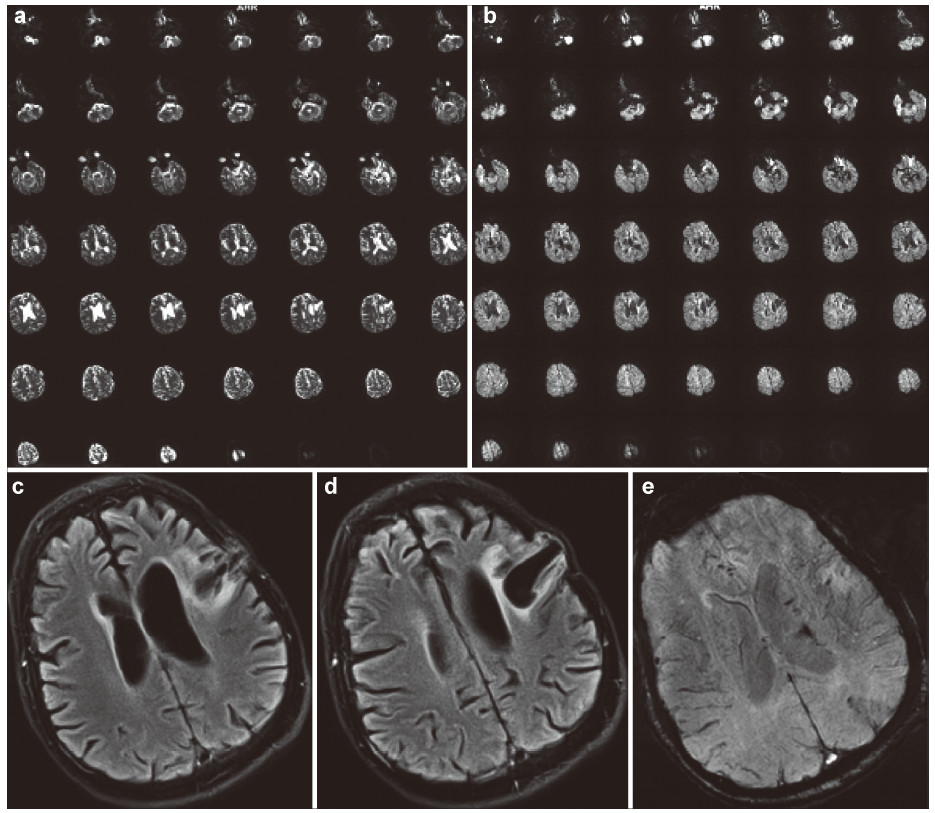

The obtained multi‐level data about the condition of the patient’s brain must be provided at contemporary carriers (CD,DVDs,flash drives,etc.) for the bioinformation analysis and they must be recorded in DICOM standard. The requirements for the research at this stage are the following: (1) No less than 1.5 Tesla MRI. (2) MRI tractography of conduction pathways in the site of injury of the brain/spinal cord. (3) MRI angiography of the brain vessels. (4) PET of the brain or a whole body,for spinal cords the standard radioisotopes of glucose PET must be done. (5) No less than 32 slice spiral CT of the brain or the spinal cord and spine. (6) Cerebral EEG mapping must be on the EEG equipment with the software for 3D local modeling of the bioelectrical activity of the brain/spinal cord. (7) MEG of the brain with 3D modeling.

The time period between different imaging tests should be not more than a week. All imaging tests that were done at the preparatory stage for the examination can be used at the next stage to monitor the effectiveness of the therapy. The imaging data can be fused into 3D maps of the brain with the help of the Multimodal fusion 3D software of the Cyberknife robotic radiosurgery system or similar systems for stereotaxic radiotherapy of other manufacturers. With this approach a three‐dimensional multi‐level mapped model of the information structure of the damaged NT of the brain/spinal cord of the nerve or mental disease case can be represented as the set of the tables of local data,that correlate them with anatomical formations in the brain so that the personalized functional 3D map of pathological changes and damages the NT of the specific case. Such a 3D map can be the basis for the marking and stereotaxic targeted therapeutic radio‐bioengineering effect of IR on the brain or spinal cord. This stage of the proposed treatment of nervous and mental diseases can be illustrated by the clinical case of the patient B. Figures 2-7 represent the data of different stages of the technology of multilevel fusion of the data of computerized tests.

|